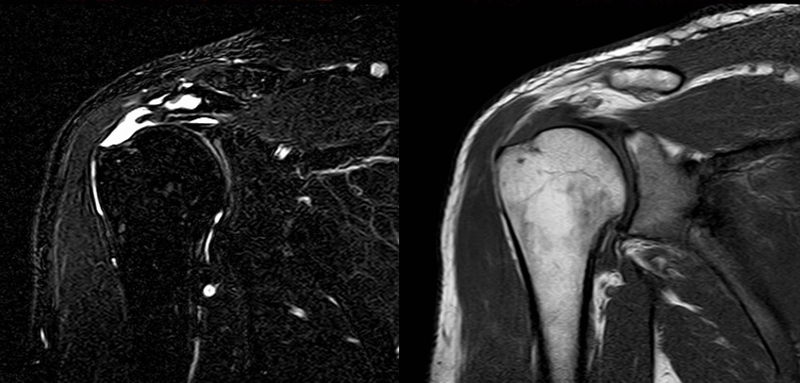

2、MRI检查

MRI目前是诊断肩袖疾病中最常用的检查,可以直观的观察肩袖肌腱。

图21 斜冠状位(临床常用)a.T2,b.T1

图24 a.肩袖全层撕裂;b.正常MRI

图25 巨大肩袖损伤(冈上肌)